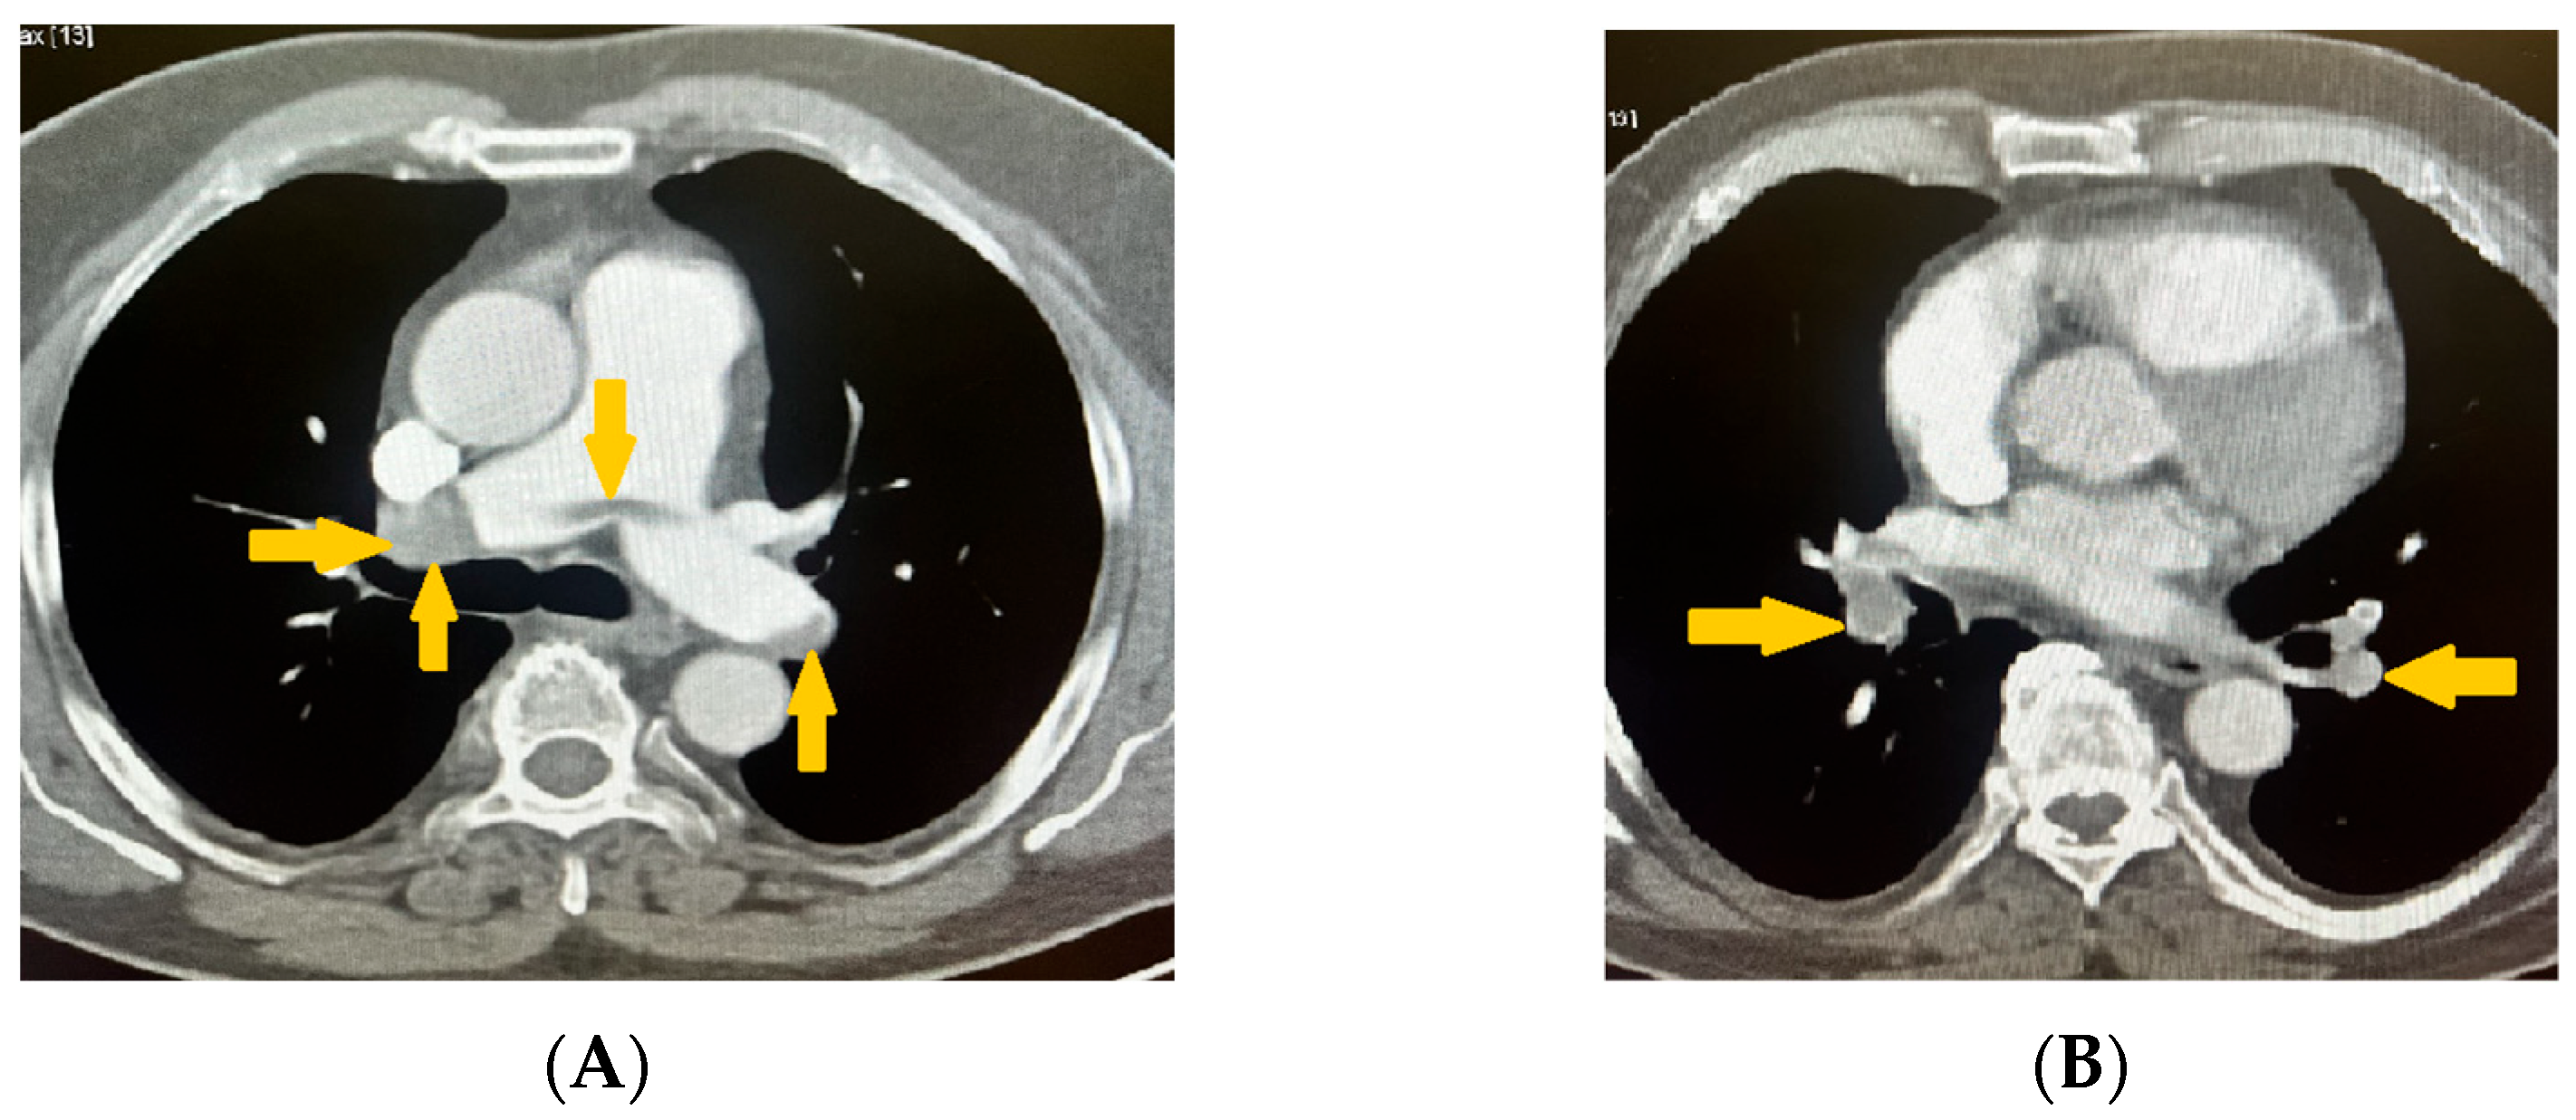

Based on the patient’s history of pain and numbness in the left leg, combined with the objective pathological findings, additional imaging of the caudal sections was analyzed. The scans revealed complete obliteration and no contrast enhancement in the left iliac artery (Figure 6A,B). Clinically, this presentation was consistent with Rutherford stage IIa–IIb acute limb ischemia (sensory deficit without major motor involvement), although this classification was not explicitly recorded in the surgical notes.

Figure 6. (A,B) Contrast computed tomography (CT) angiography scans revealing complete obliteration and no contrast enhancement in the left iliac artery (blue arrows).